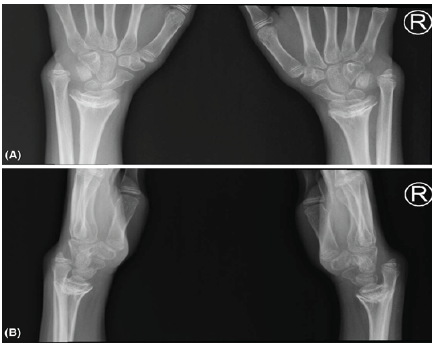

No point tenderness at the level of the elbow or shoulders. His distal neurovascular status intact. Furthermore, there was a positive ulnar ballottement test and a positive ulnar impaction test as well. Comprehensive radiological investigations, including X-Rays (Fig. 1), and magnetic resonance images revealed multiple abnormalities.

Figure 1: (a) Pre-operative of bilateral wrist X-ray anteroposterior view. (b) Pre-operative of bilateral wrist X-ray lateral view.